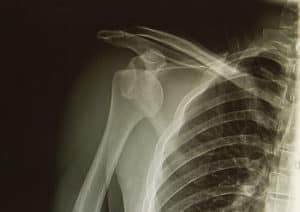

What Is A Closed Reduction Procedure? | AICA OrthopedicsWhen shoulder dislocation occurs, a closed reduction procedure is required to place the shoulder back into the socket. Most often, this type of process takes place in an emergency room.

For most dislocations, shoulders can be repositioned without surgery using a closed reduction procedure. The doctor will administer an anesthetic to help minimize the pain and then manually reposition the humerus into the shoulder socket.

Almost immediately following the repositioning of the shoulder, the pain will diminish. The procedure from start to finish takes about 30 minutes, and following a follow-up x-ray, patients can return home.